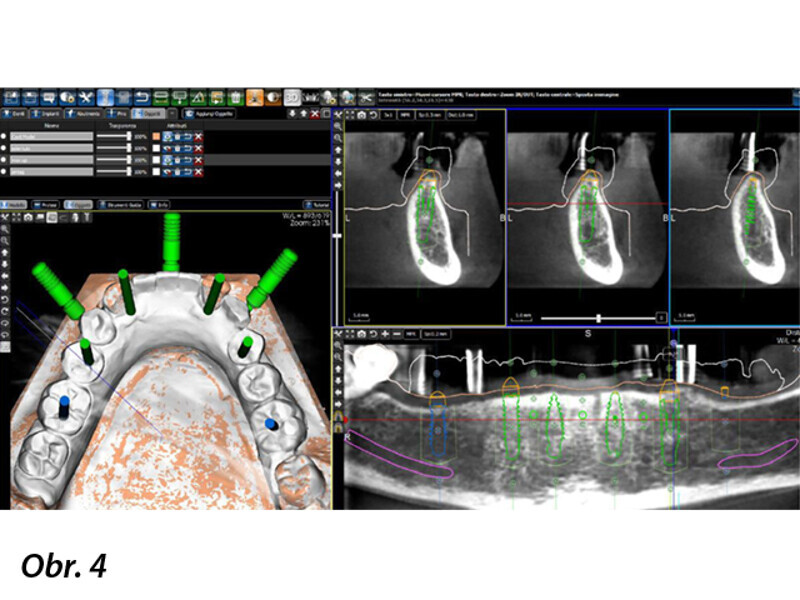

Počítačem asistované, šablonou se řídící okamžité zavedení a zatížení implantátu v dolní čelisti